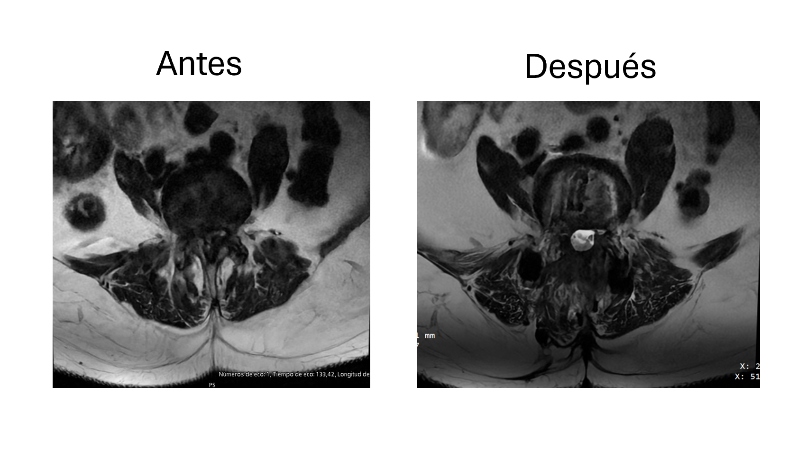

Abordaje cervical anterior con colocación de caja intersomatica C5-C6

Después de años con dolor intenso y limitación en el cuello, me realizaron un abordaje cervical anterior con colocación de caja intersomática en C5-C6. La recuperación fue rápida y el alivio fue casi inmediato. Volví a mis actividades sin molestias. Estoy muy agradecido con el equipo médico.